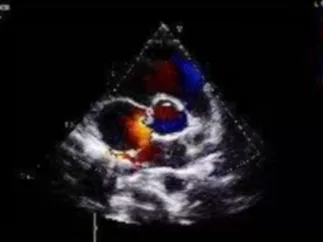

锁定后评估

心尖四腔心切面可见封堵器形态良好

主动脉短轴切面可见封堵器呈“Y”字型抱住主动脉

彩色多普勒血流成像显示无残余分流存在